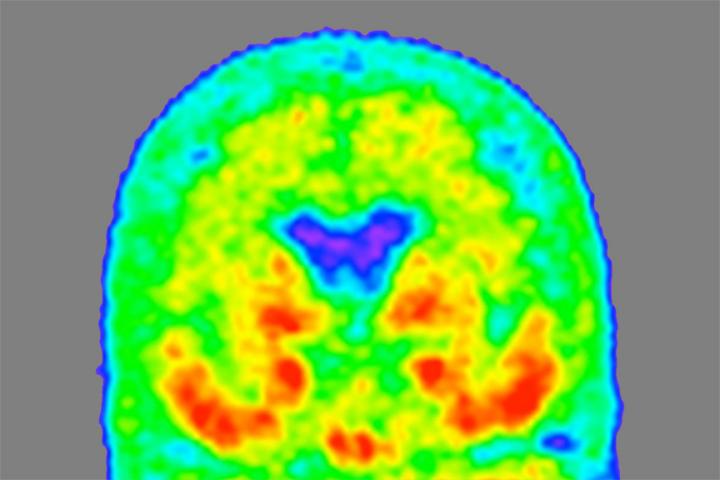

image: A "heat map" of the brain of a person with mild Alzheimer's dementia shows where tau protein has accumulated, with areas of higher density in red and orange, and lower density in green and blue. Researchers at Washington University School of Medicine in St. Louis have found a form of tau in spinal fluid that tracks with tau tangles in the brain and indicates what stage of the disease a person is in.

Tammie Benzinger/Knight ADRC